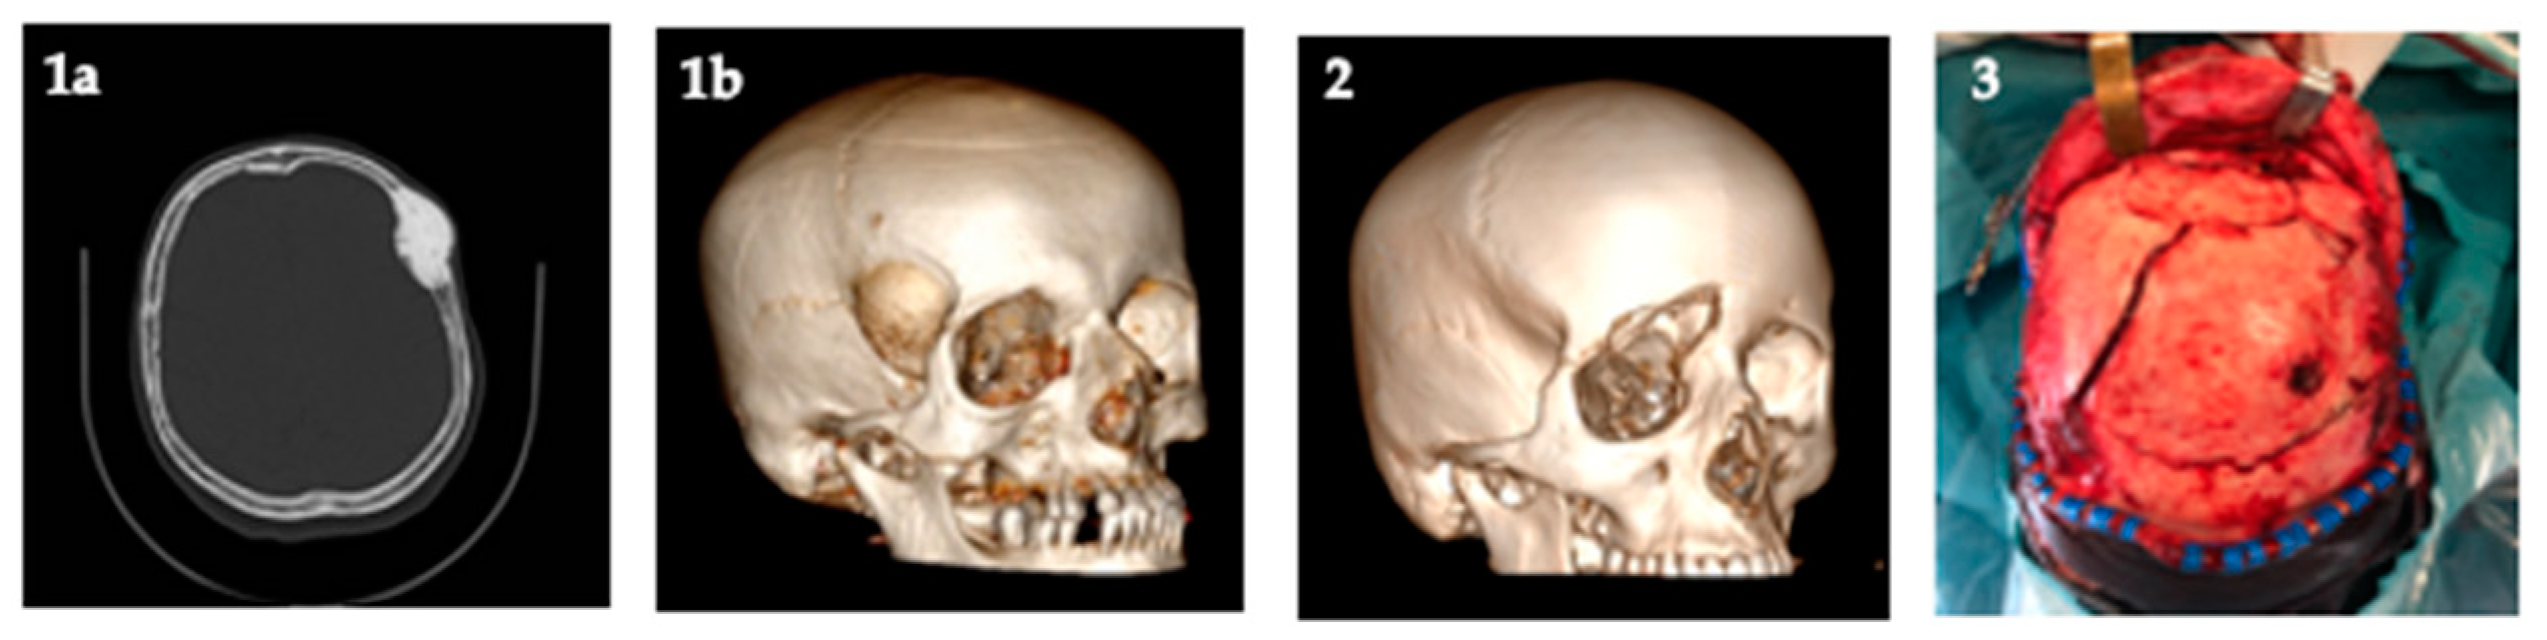

Figure 1.

Example of causes that require cranioplasty (authors personal database images): (1a) axial computerized tomography (CT) scan of tumor involving cranial bone; (1b) 3D-CT scan of tumor involving cranial bone; (2) 3D-CT scan of depressed skull fracture; (3) surgical exposition of complex depressed skull fracture.